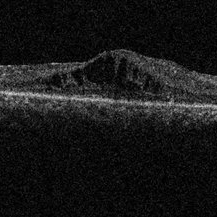

Choroidal Osteoma  + CNV Choroidal Osteoma  + CNVMar 13 2013 by Hamid Ahmadieh, MD Optical coherence tomography (OCT) of the right eye of a 13-year-old girl with decreased VA due to CNV secondary to choroidal osteoma. Photographer: Naghmeh Nozhat, Negah Eye Center, Tehran Imaging device: Topcon Condition/keywords: choroidal neovascularization (CNV), choroidal osteoma, optical coherence tomography (OCT)